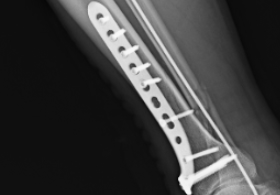

近日,41歲的貨車司機(jī)韓師傅在搬運(yùn)貨物時(shí),因貨物太重不慎摔倒,右腿扭傷。同事們立即撥打120,將他送往紹興袍江醫(yī)院急診科。到達(dá)醫(yī)院時(shí),韓師傅的右小腿已經(jīng)明顯腫脹變形。急診科醫(yī)生迅速為他安排了檢查,結(jié)果顯示"右側(cè)脛腓骨遠(yuǎn)段多發(fā)骨折"。作為家中的頂梁柱,這個(gè)診斷讓韓師傅心情沮喪——他擔(dān)心漫長(zhǎng)的康復(fù)期會(huì)影響工作,更擔(dān)心留下后遺癥。骨科李志龍主任醫(yī)師團(tuán)隊(duì)會(huì)診后,立即為韓師傅制定了詳細(xì)的手術(shù)方案。次日,在椎管內(nèi)麻醉下,李志龍主任主刀為韓師傅施行了"右脛腓骨2025-11-10

-